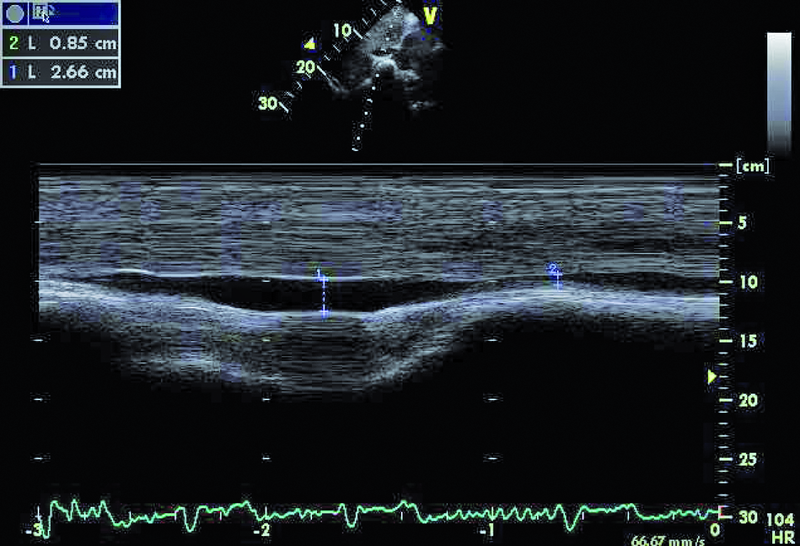

Kobieta, lat 80. Jakie patologie można rozpoznać na rycinach?

1. Powiększenie jamy prawej komory (ryc. 1).

2. Przerost mięśnia lewej komory (ryc. 1).